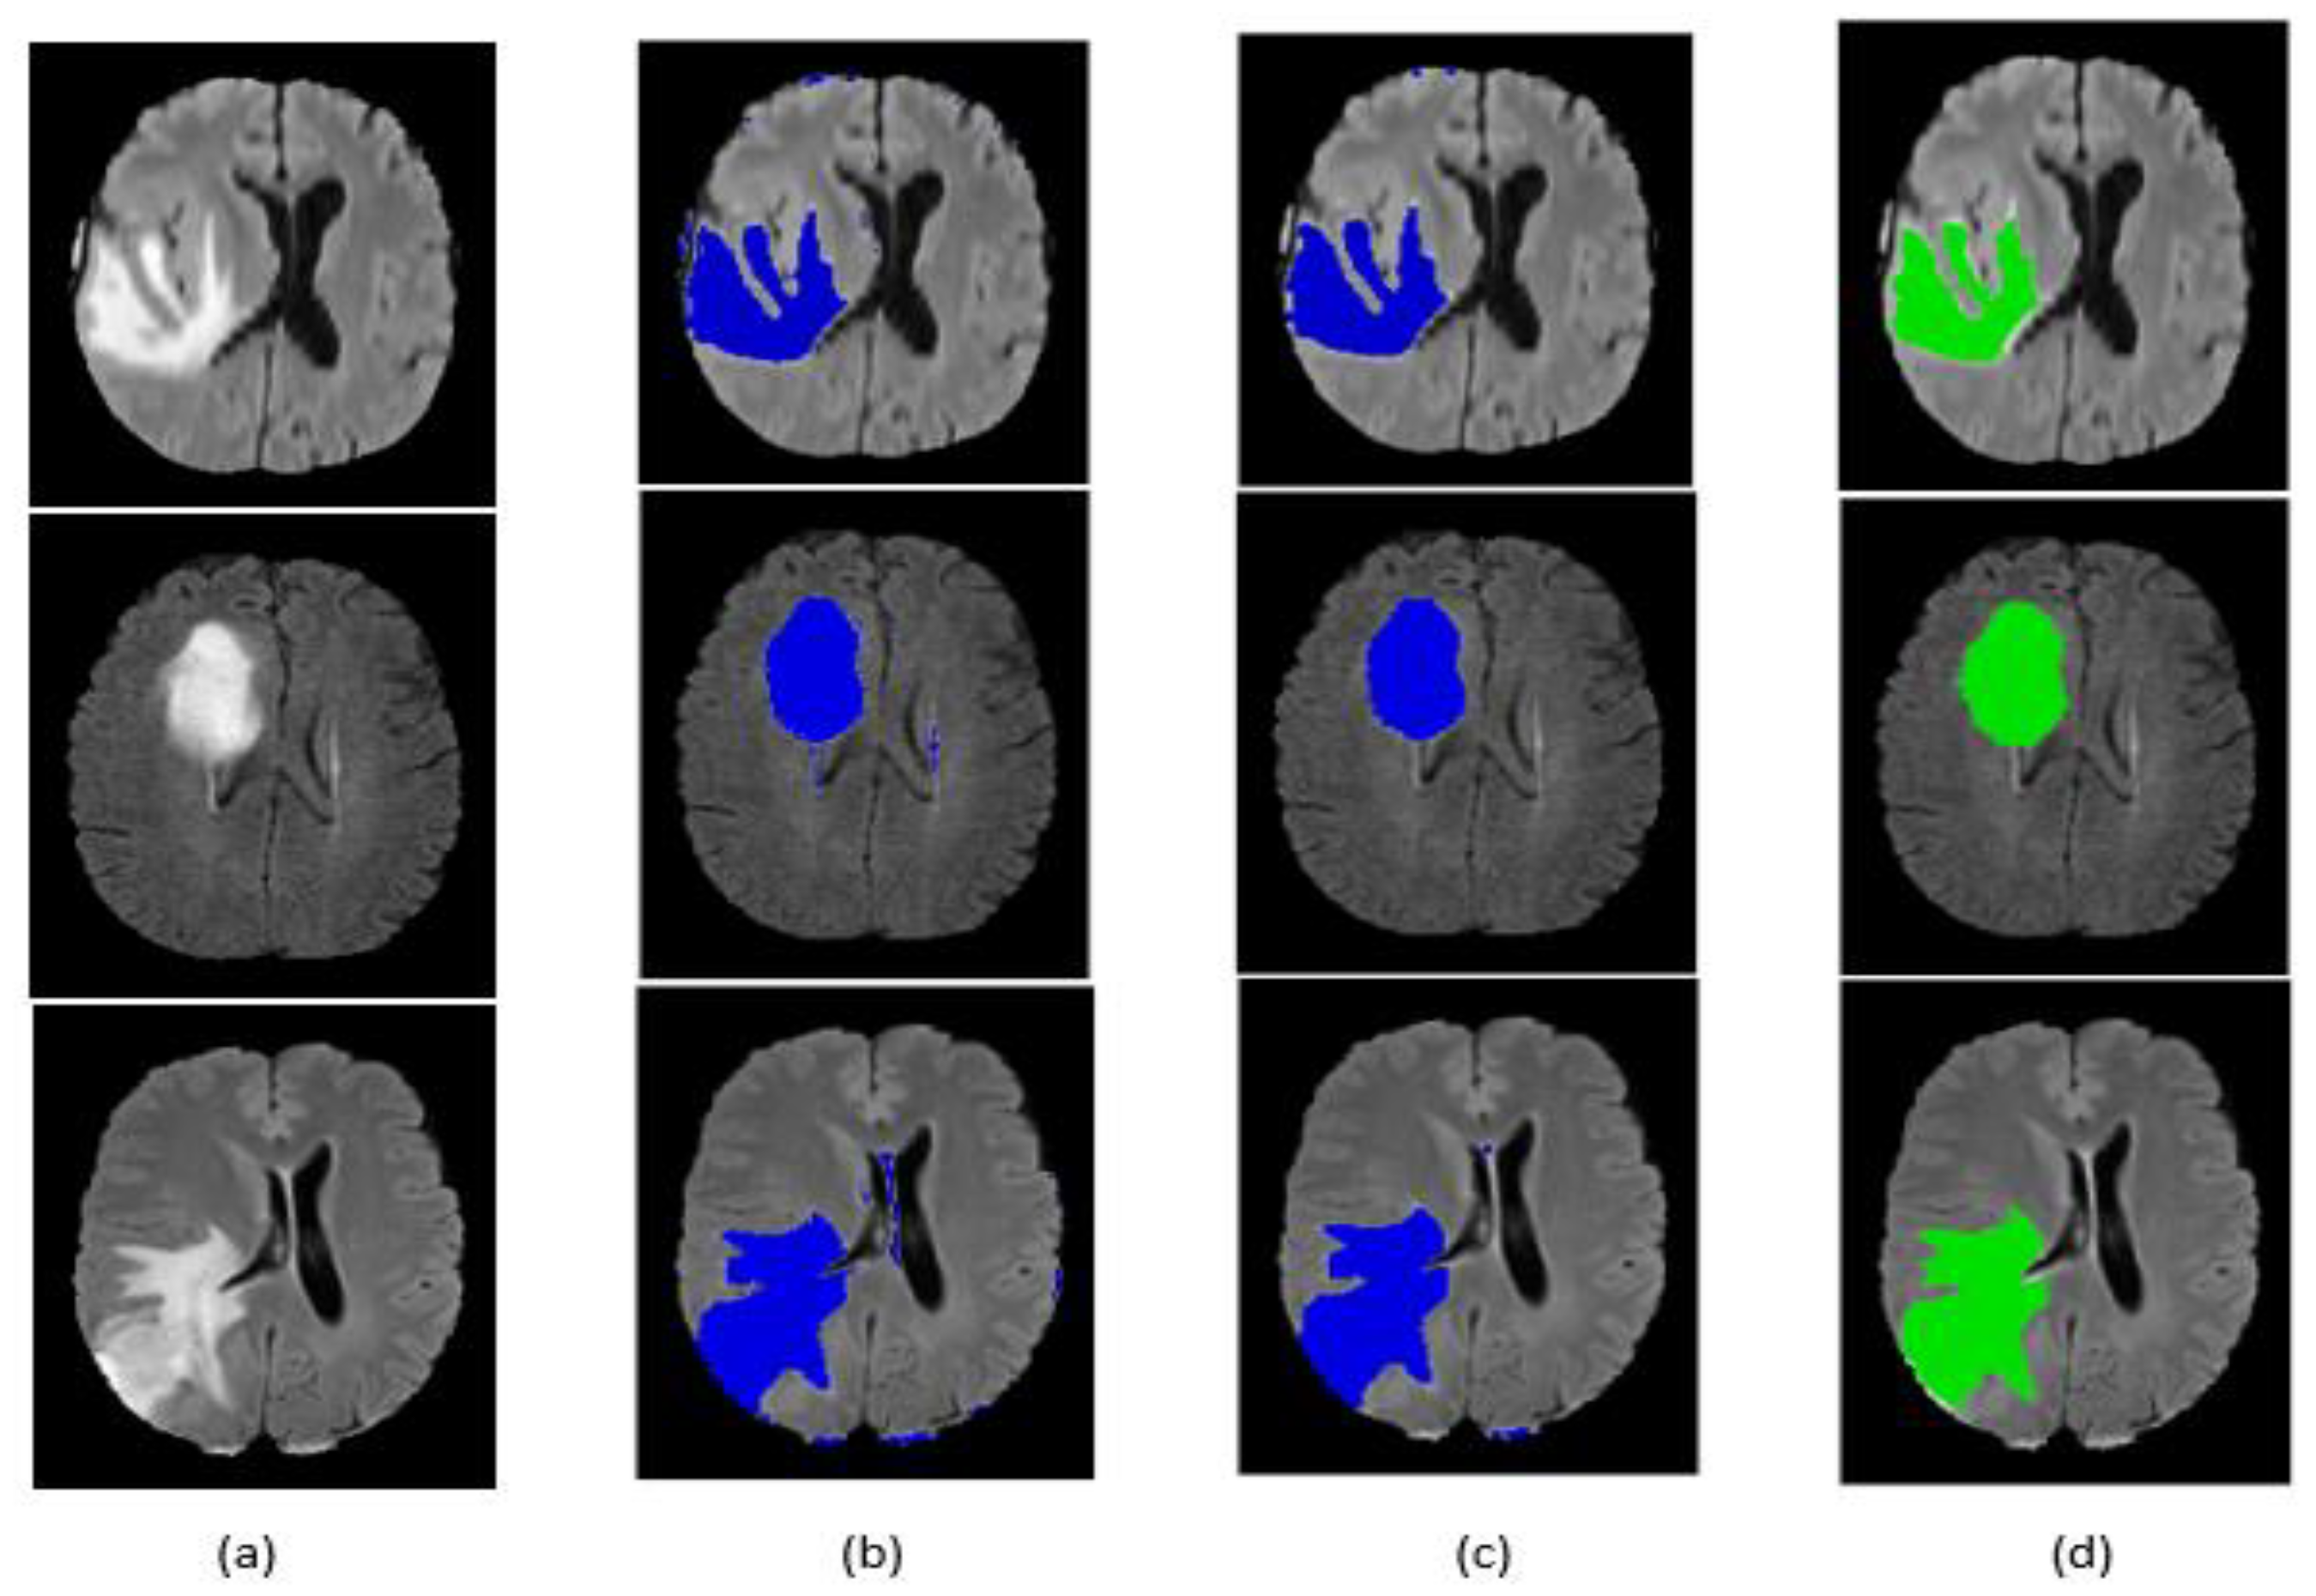

Qualitative segmentation results are presented in Figure 9 and Figure 10 for the BraTS 2017 dataset. The figures also indicate that our network is capable of accurately segmenting complete tumor regions. Our approach was tested on the FLAIR modalities for MRI images outside the BraTS 2017 dataset, and it provided good results, which guarantees the performance and power of the proposed method.

Figure 9.

Segmentation result of our method on some BraTS 2017 HGG images: (a) original image, (b) segmentation before post-processing, (c) segmentation after post-processing, (d) ground truth.